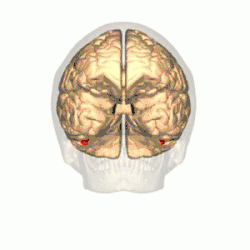

Additional images

Fusiform face area shown in red